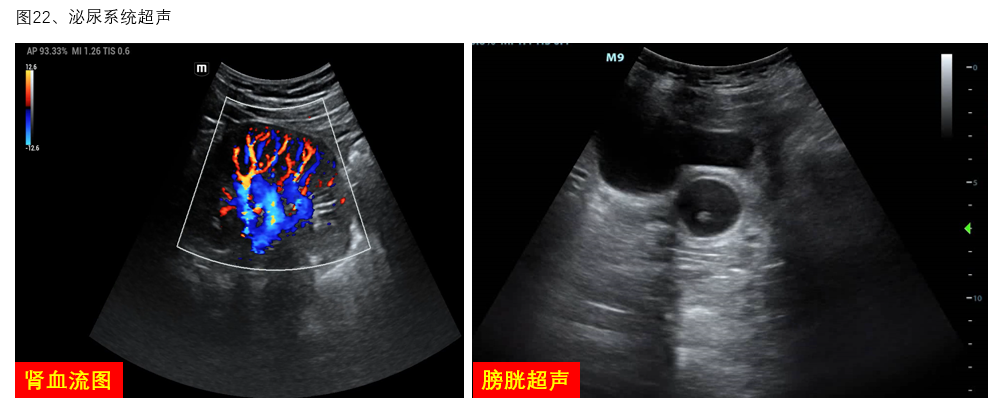

6、泌尿系超声:肾脏血流图可协助评估肾灌注情况,调节VA-ECMO流量,并明确发生AKI的原因。在实施过程中,对输尿管、膀胱的探查可快速明确少尿/无尿的肾后性梗阻因素(图22)。

图22 泌尿系统超声